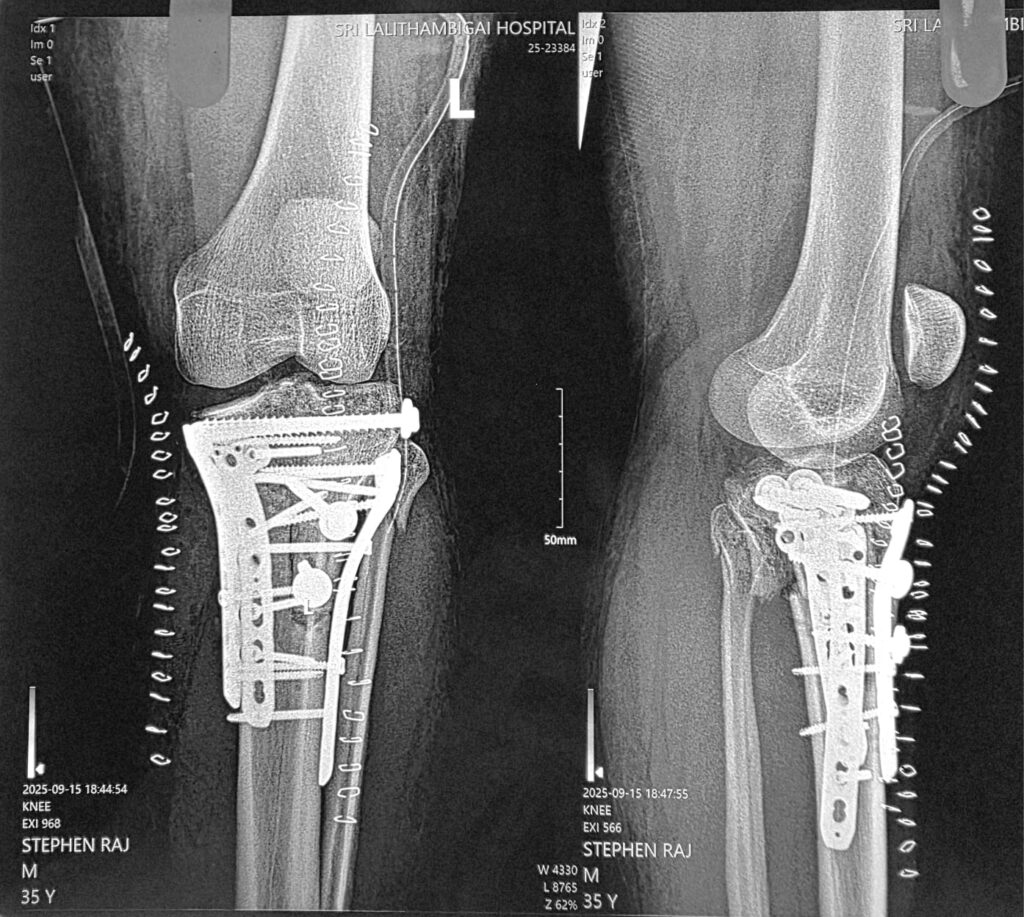

Posteromedial tibial plateau # and lateral tibial plateau #. Also, ligamentum patellae avulsion with tibial tubeorsity. Posterior approach medially and anteromedial approach anteriorly. 3 plates and 2 cancellous screws with washers to fix tibial tuberosity. Patient also had calcaneal # , fracture of radius and fracture of both bones of opposite lower limb. All operated in 2 sittings. This was following a RTA. Needed a lot of planning. Patient did well.

ORIF for communited # tibialateral

This is the communited fracture of the tibia lateral plateau and medial plateau which has been fixed with lateral and postro medial plates. Good reduction achieved